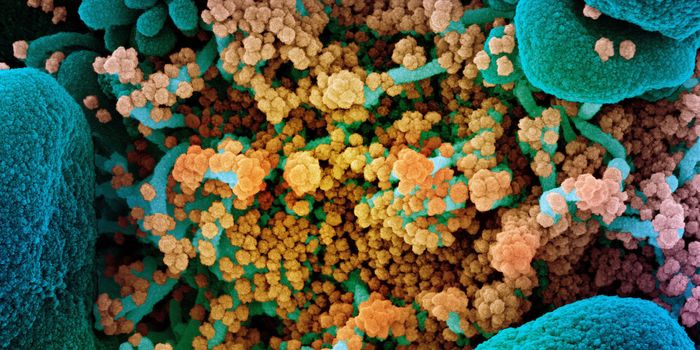

MAY 03, 2020Genetics & GenomicsThe origin of SARS-CoV-2, the pandemic virus that causes COVID-19, has become politicized as leaders seek to place blame ...

JUL 06, 2020MicrobiologyThe pandemic coronavirus has caused a wide range of different symptoms, and as time goes on, we may find that it can hav ...

JUL 05, 2020Cell & Molecular BiologyThe pandemic virus SARS-CoV-2 enters the body through the respiratory system to cause the illness COVID-19. But we know ...

JUN 29, 2020MicrobiologyVaccines that contain live attenuated viruses may be giving people some protection from serious cases of COVID-19 that i ...

FEB 22, 2021MicrobiologyReporting in Science, researchers have created an antiviral nasal spray that could help us get the COVID-19 pandemic und ...

SEP 01, 2021MicrobiologyIt's been generally assumed that people who get infected with SARS-COV-2 will develop antibodies to the virus, which cau ...

MAR 18, 2020MicrobiologySARS-CoV-2 is a coronavirus that causes an illness called COVID-19. There are now well over 210,000 confirmed cases worl ...